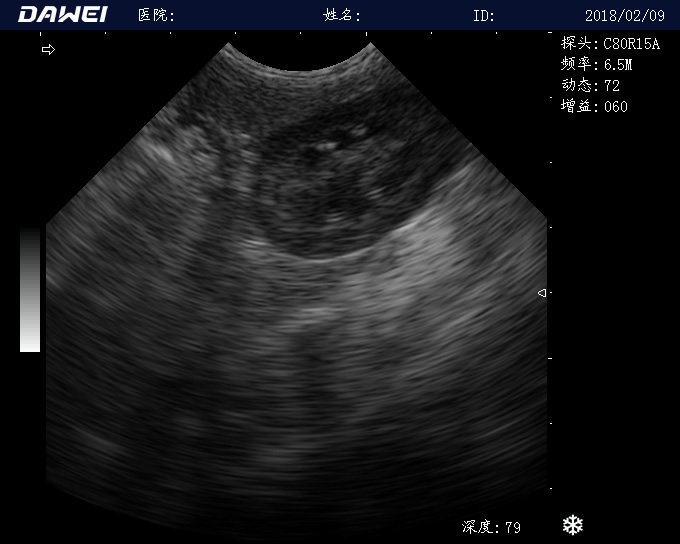

MT15推车式兽用B超仪

全数字动物超声诊断仪

·探头频率:支持≥5种变频,临床效果更好体现

·中小动物的肝、胆,脾、肾、膀胱、子宫、妊娠等各组织器官的检查和病变的诊断